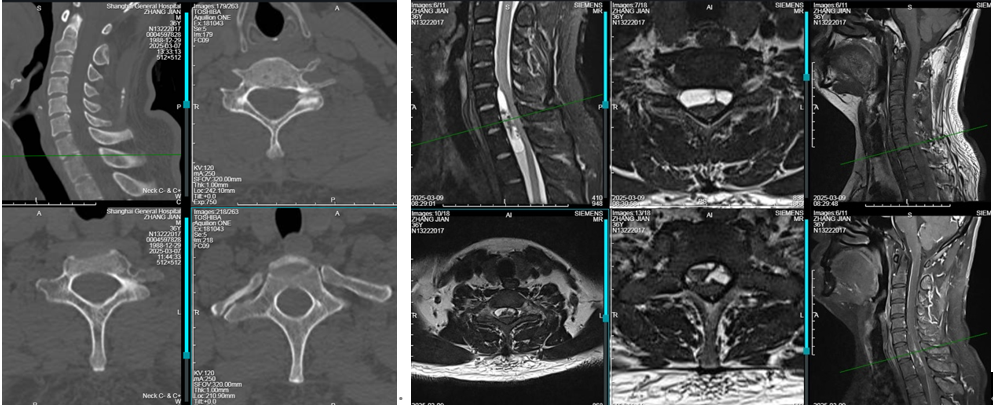

患者5年余前无明显诱因下出现颈部僵硬不适,双上臂、背部牵拉痛,一直未予重视。近一月来症状加重,并出现双侧上肢放射痛疼,无力、麻木等表现。于当地医院就诊,行颈椎CT、MRI检查提示:平颈6、7胸1椎体段脊髓前方异常信号影,占位待排。

CT:C6-T1椎管内硬膜囊前缘受压,相应骨性椎管未见破坏。

增强MRI:C6-T1水平椎管内前侧硬膜下见条片囊实性占位,累及长度约53mm,囊性成分为主,内见少许T1WI高、T2WI低信号、出血信号,增强后病灶边缘及内部条片样强化为主,相应阶段脊髓受压狭窄。

影像诊断:C6-T1水平椎管内前侧那硬膜下囊实性肿块,神经源性肿瘤可能。

初步诊断:C6-T1髓外硬膜下肿瘤(考虑神经鞘瘤)